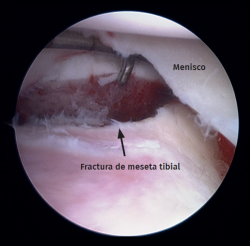

Figure 2. Right knee, Schatzker II tibial plateau fracture. Step-off arthroscopic view from the anteromedial portal. Probe placed in the anterolateral portal.

Standard anterolateral and anteromedial portals are created adjacent to the patellar tendon and the joint is visualized with a 30° arthroscope while the knee is insufflated with normal saline. A diagnostic arthroscopy is performed to confirm the TPF, the step-off and the presence of associated lesions (Figure 2). An arthroscopic shaver is inserted into the knee to clear the debris and improve visualization. Next, a small longitudinal anterolateral skin approach is performed, and the fractures are fixed with cancellous screws and/or a buttress plate applied on the external side (minimally invasive plate osteosynthesis), according to the type of fracture diagnosed (Figure 3). Arthroscopy is used to assist reduction and, when needed, to treat soft tissue injuries. The senior authors prefer to perform meniscal repair or partial meniscectomy before bone fixation due to the better visualization of the meniscus. Conversely, ligamentous reconstructions are performed after arthroscopically assisted fixation to ensure bony stability.